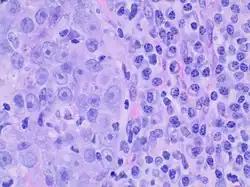

On histopathology, medullary breast carcinoma is characterized by groups of tumor cells with syncytial appearance (that is, seemingly fused cytoplasms, at left). There is typically also a lymphocytic and plasma cell infiltrate (right).[5]

Criteria must be met through the Ridolfi criteria. Although there are other classifications for diagnosis, the Ridolfi criteria are the most commonly used. There must be histologic evidence of lymphoplasmacytic infiltration, noninvasive microscopic circumscription, greater than 75% syncytial growth pattern, and high-grade nuclei.[5] It is immunologically typically triple-negative, with negative estrogen receptors (ER), negative progesterone receptors (PR), and negative HER2/neu receptors.[3] There are also medullary breast carcinomas that are found to be estrogen receptors (ER) and/or progesterone receptor (PR) positive, making diagnosis less straightforward.